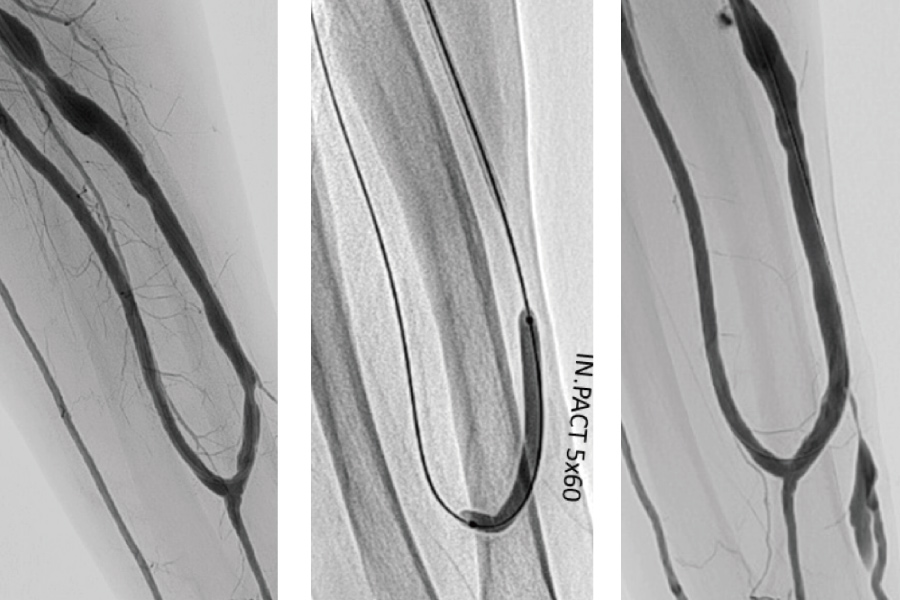

透析患者様にとって、シャントは生命線です。シャントは週3回、数時間使用しますが、バルーン拡張のみでは再び狭くなることも多く、3か月ごとなど定期的な治療が必要になる患者様もいます。私たちは、狭くなりにくい薬剤塗布型バルーンや人工血管を用いて、長い開存性を目標とした治療を行っています。この薬剤塗布型バルーンにおいては、国内で治験が行われた際、私も治験の責任者として参加しましたが、通常のバルーンと比べて長期間の効果を維持することが証明されています。

通常のバルーン

薬剤バルーン